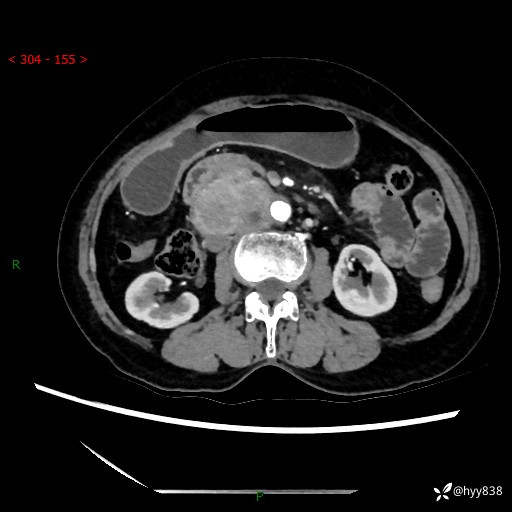

71岁/女,腹痛1月余。腹膜后肿物,间质瘤 VS 副节瘤 VS 平滑肌肉瘤---(有结果)

【患者信息】:71岁/女

【主诉】:腹痛1月余

【检查】:腹部CT增强扫描(外院CT平扫)